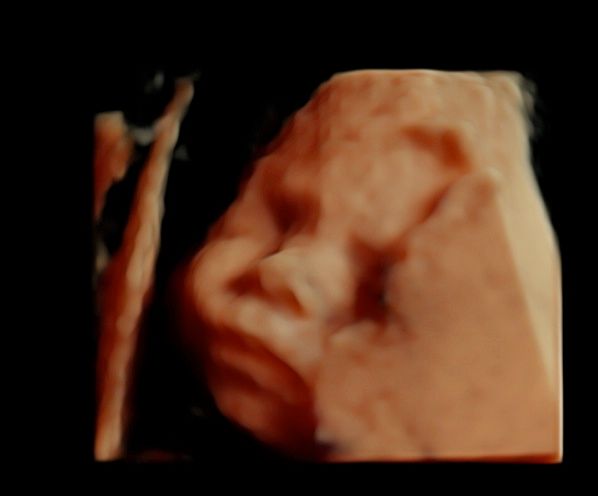

Foto e video

• Ecocardiografia fetale

• Ecografia morfologica